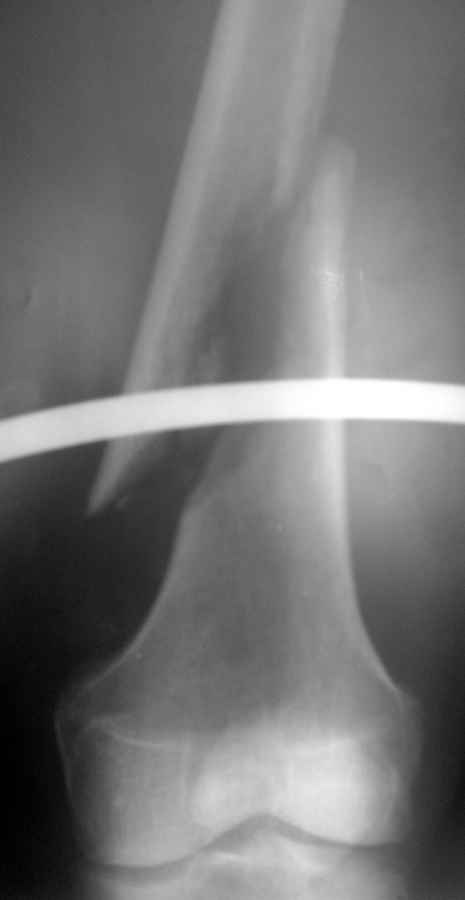

Доброго времени суток. 12.04.2011г. поступил пациент 64 лет, с косым переломом правой бедренной кости в нижней трети со смещением отломков.

Из анамнеза: начали беспокоить боли в правом бедре, в течение месяца лечился амбулаторно (НПВП, физиолечение) - без эффекта, боли нарастали. 12.04.2011г. при ходьбе наступил патологический перелом бедра, "Скорой" доставлен в стационар. Rg-снимки в приложении. Клинически имеется припухлость в нижней трети, болезненная при пальпации. Опухоль? Обследуем. Больше ничего по онкопатологии нигде не нашли. Сегодня - подъем температуры до 39гр, бедро в области перелома на ощупь горячее, флюктуация по наружной поверхности. При пункции получен зловонный гной. Взяты посевы, анализ на цитологию, начато консервативное лечение острого гематогенного остеомиелита.